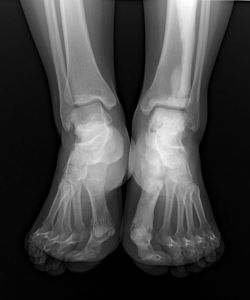

蠟油樣骨病從X線平片看出,蠟油樣骨病患者的髖部主要表現為一側髖關節兩端骨質增生硬化,呈斑片狀或團塊狀高密度影,病變可跨越髖關節.但關節腔及關節面保持正常,髖關節周圍軟組織口見異位骨化。表現為骨內有斑點狀或條紋狀緻密影,不易引起輪廓改變,關節多不受影響,即使關節兩端骨質發生明顯新骨堆積,關節面仍保持光滑,附近軟組織中常有骨質沉積。